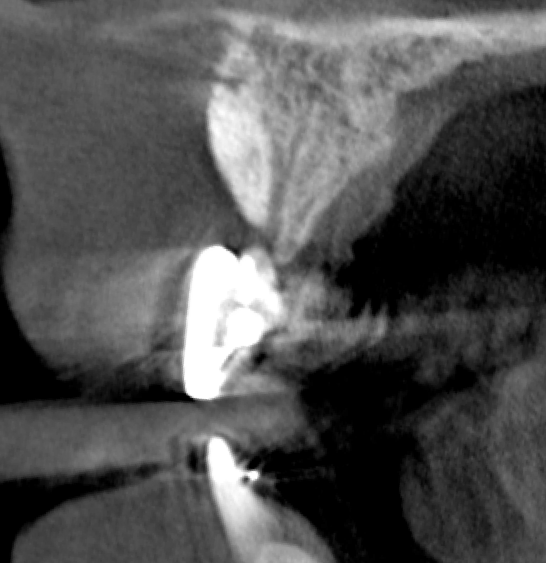

Tomographic images revealed a large tridimensional defect, with vertical and horizontal loss of bone extending to the apical third of teeth Nos. 6 and 8. Additionally, a buccal bone dehiscence was evident on tooth No. 5, and thin labial plates secondary to the orthodontic movement were present in several areas (Figure 3 and Figure 4).

After 3 months of post-orthodontic stabilization, a cone-beam computed tomography scan was taken to re-evaluate the results and plan the future treatment sequence. Tomographic images clearly showed vertical gains in alveolar height, including in the edentulous area corresponding to tooth No. 7 (Figure 10 through Figure 12). The apex of tooth No. 8 was forced-erupted beyond its socket and could be visibly located within the soft tissue.30,33